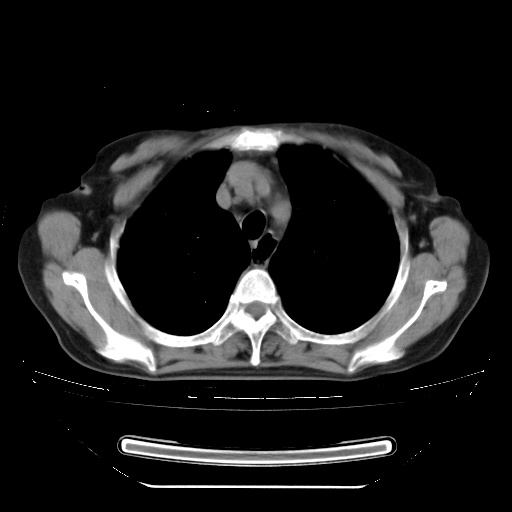

两肺内病灶呈小结节状和树芽状,纵膈的肿大的淋巴结密度不均匀,并见有钙化,考虑为两肺结核可能更大些。

两肺内病灶呈小结节状和树芽状,纵膈的肿大的淋巴结密度不均匀,并见有钙化,多形态病灶,考虑为两肺结核,肝内考虑小囊肿。

片子很好,质量很高,两侧肺门淋巴结肿大并有钙化,两肺弥漫病灶,首先考虑tb并播散,但年龄大了呀(72岁)小细胞肺癌不能除外,如果是肺癌也没什么大的治疗了,建议正规抗结核治疗后复查

纵隔见肿大淋巴结并钙化,首先考虑结核,但感觉小结节像“挂果”征,分布位于支气管边缘,所以不排外肺泡癌,建议抗唠后复查吧?不然是癌的话,也不好治吧?化疗?